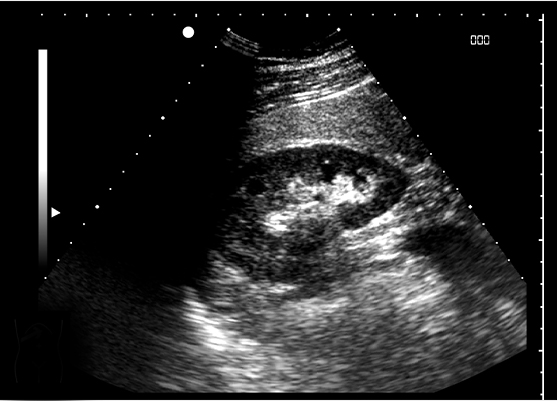

신장 초음파

초음파 검사는 조영제에 대한 부작용이나 알레르기 등을

유발하는 환자와 임산부, 소아 등 방사선 촬영이

힘든 환자들을 대상으로 시행되는 방법으로

초음파 검사 시 결석은 하얗게 나타납니다.